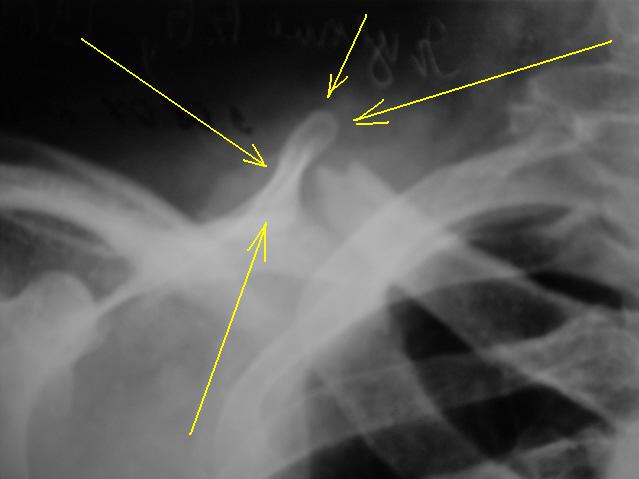

А как трактовать помеченное желтыми стрелками?

А это верхний угол лопатки. Такое впечатление, что он образует с проксимальным отломком ключицы что-то типа неоартроза.

Вот мне тоже примерно такое и кажется, но что-то не совсем мне понятно.

А что, все очень похоже......есть "импровизированная" суставная впадина, образовавшаяся из верхнего угла лопатки, и с ней сочленяется отломок ключицы, все довольно конгруэнтно